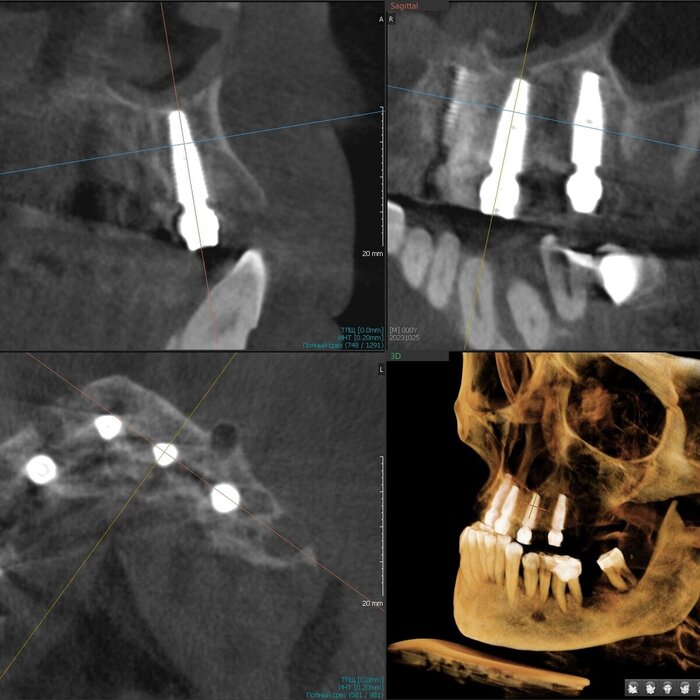

Как же всё-таки у нас происходит это мероприятие? Так как мы вмешиваемся в другую область нашего тела, то стоматолог должен быть хоть немного лором. Разумеется, всё начинается с обследования, которое включает в себя трехмерный снимок, который, в идеале должен захватывать не только зубы и область наращивания, но и носовые ходы с устьями гайморовых пазух и прочими загогулинами, то есть, так называемый остиомеатальный комплекс.

Поэтому кастрированный снимок, где видна только область установки будущего имплантата не прокатит. Тем более в центрах КТ такой снимок стоит дороже классической КТ рублей на 200. И стоит ли экономить?

Анализируя снимок, мы должны принять решение о том можно ли делать синус-лифтинг или отправить его на консультацию к лору. Если всё хорошо, то планируем операцию.